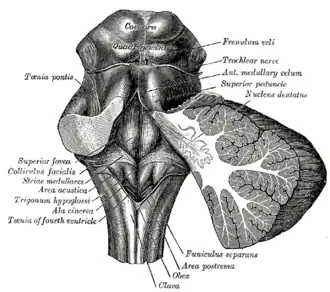

Rhomboid fossa. (Area postrema labeled at bottom center.) | |

Human caudal brainstem posterior view description (Area postrema is #8) | |

Structure

The area postrema is a paired protuberance found at the inferoposterior limit of the fourth ventricle.[1][5] Specialized ependymal cells are found within the area postrema. These cells differ slightly from the majority of ependymal cells (ependymocytes), forming a unicellular epithelial lining of the ventricles and central canal. The area postrema is separated from the vagal trigone by the funiculus separans, a thin semitransparent ridge.[1][5] The vagal trigone overlies the dorsal vagal nucleus and is situated on the caudal end of the rhomboid fossa or 'floor' of the fourth ventricle. The area postrema is situated just before the obex, the inferior apex of the caudal ventricular floor. Both the funiculus separans and area postrema have a similar thick ependyma-containing tanycyte covering. Ependyma and tanycytes can participate in the transport of neurochemicals into and out of the cerebrospinal fluid from its cells or adjacent neurons, glia or vessels. Ependyma and tanycytes may also participate in chemoreception.[1][5]